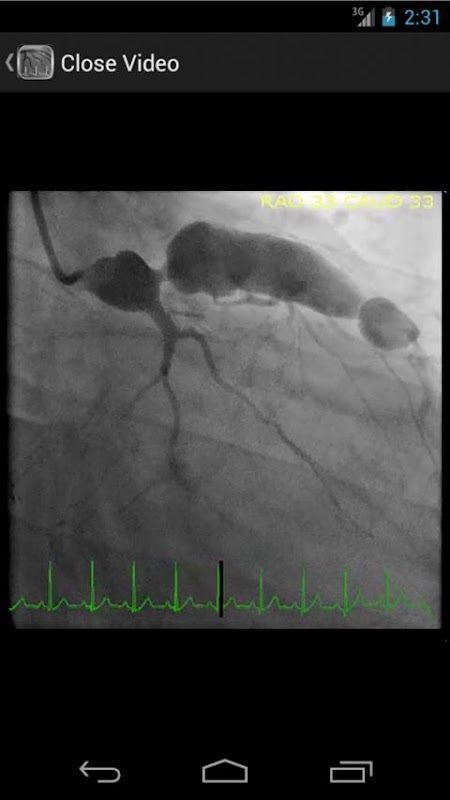

* Durchsuchbare Datenbank mit mehr als 30 Videos (koronare Angiographien, ventriculograms und aortograms) beider gemeinsame und seltene Befunde im Herzkatheterlabor

CathSource bietet einen detaillierten Überblick über wichtige Herzkatheter und Angiographie Themen unter Einbeziehung Bildungs Bilder / Videos sowie Bewertungen der einschlägigen medizinischen Literatur. CathSource ist die ideale Anwendung, um Sie zu verstehen und zu erkennen, kardiovaskuläre Pathologie im Katheterlabor zu unterstützen.